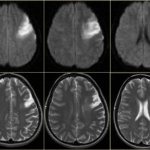

У больных возникают проблемы со зрением, слухом им трудно на чём-то сконцентрировать внимание. Повышается артериальное давление. Возможно появление язвы желудка. Часто образуются тромбы. Головной мозг недополучает необходимого кислорода и увеличивается опасность инсульта. При возникающей анемии кожа бледнеет, кружится голова.

Эритремия – заболевание крови, которое на третьей стадии становится агрессивным. На данном этапе клетки костного мозга подвергаются фиброзу. Он уже не может вырабатывать эритроциты, поэтому нормы форменных элементов крови падают, порой до критических показателей. В головном мозге появляются очаги размягчения, начинается фиброз печени. В желчном пузыре находится густая, вязкая желчь и пигментные камни. Следствием этого является цирроз печени и закупорка сосудов.

Раньше именно повышенное тромбообразование становилось причиной смерти больных эритремией. Стенки сосудов подвергаются изменениям, наблюдается закупорка вен в сосудах мозга, селезенки, сердца и ног. Возникает облитерирующий эндартериит – закупорка сосудов ног с риском их полного сужения.

В зависимости от того, в каких сосудах происходит тромбоз, может развиваться клиника острого живота, гангрены нижних или верхних конечностей, тромбоза легочной артерии с кровохарканьем, инфаркта миокарда, инсульта головного мозга.